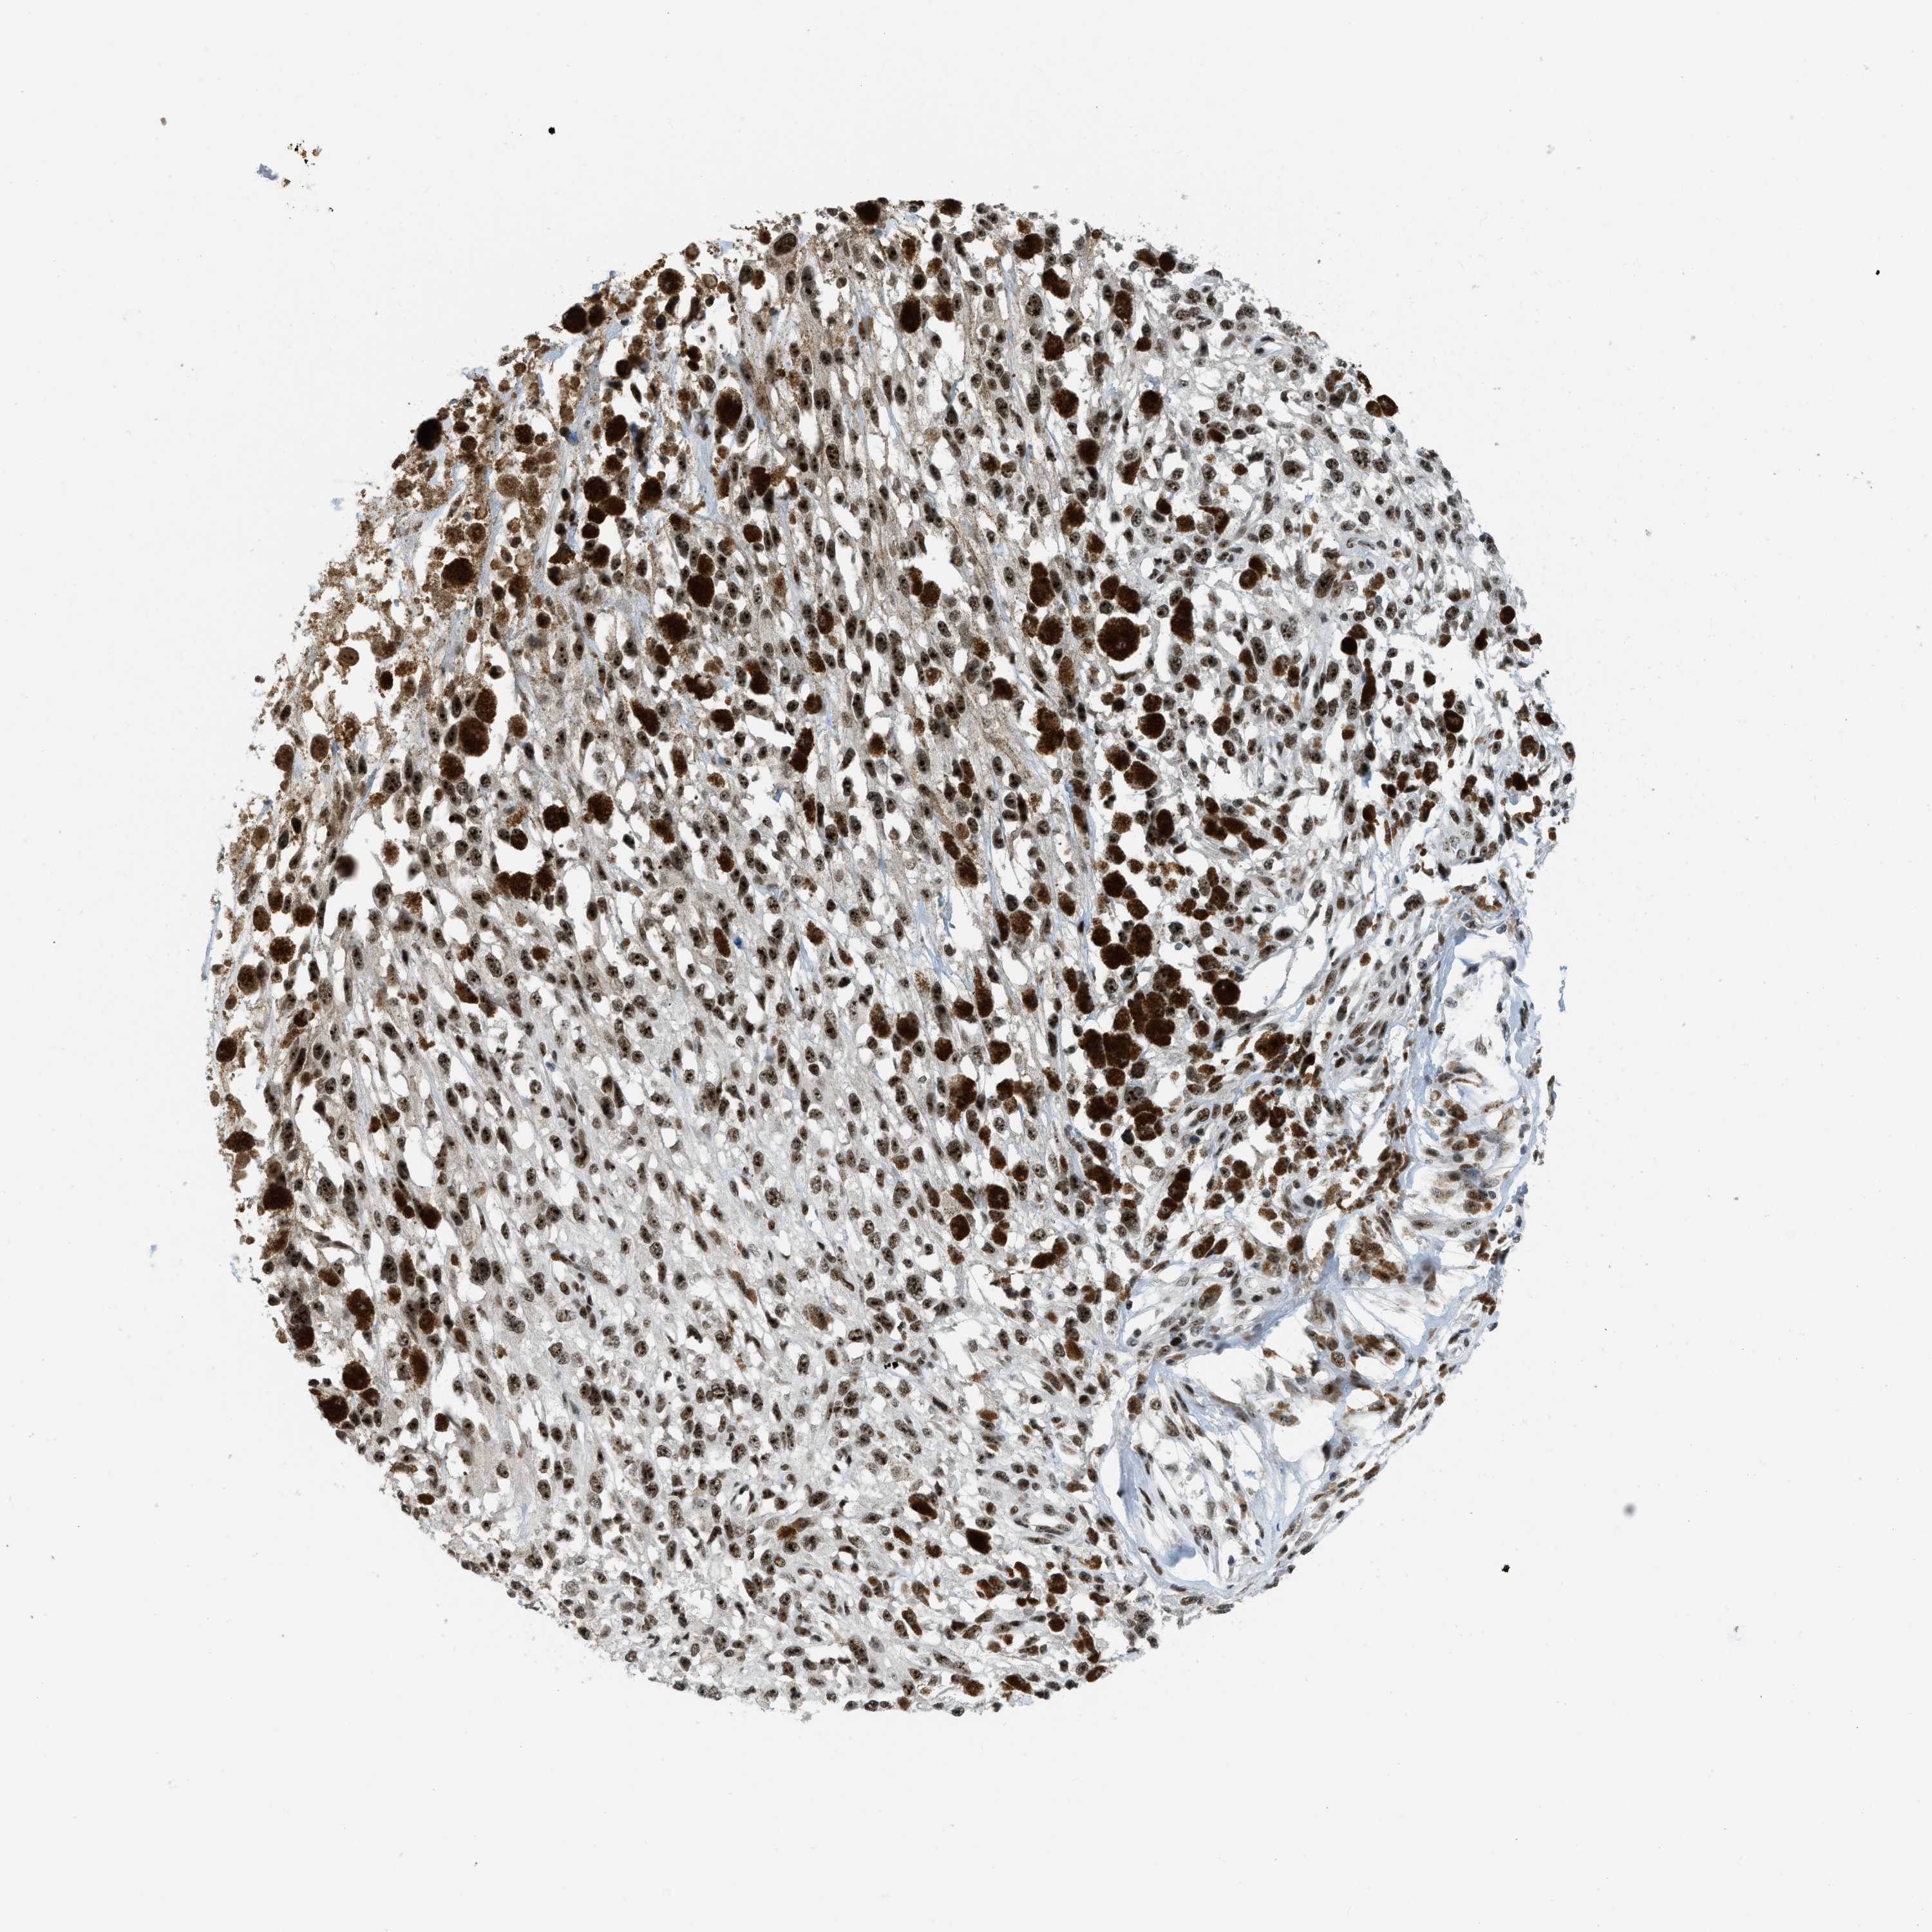

MELANOMA - Protein expressioni

A mouse-over function shows sample information and annotation data. Click on an image to view it in a full screen mode. Samples can be filtered based on level of antibody staining by selecting one or several of the following categories: high, medium, low and not detected. The assay and annotation is described here.

Note that samples used for immunohistochemistry by the Human Protein Atlas do not correspond to samples in the TCGA dataset.

Antibody stainingi

Antibody staining in the annotated cell types in the current human tissue is reported as not detected, low, medium, or high, based on conventional immunohistochemistry profiling in selected tissues. This score is based on the combination of the staining intensity and fraction of stained cells.

Each image is clickable and will lead to virtual microscopy that enables deeper exploration of all samples and also displays staining intensity scores, fraction scores and subcellular localization as well as patient and tissue information for each sample.

Antibody HPA018334

Staining

High

Medium

Low

Not detected

Intensity

Strong

Moderate

Weak

Negative

Quantity

>75%

75%-25%

<25%

None

Location

Nuclear

Cytoplasmic/membranous

Cytoplasmic/membranous,nuclear

Malignant melanoma, NOS

Malignant melanoma, Metastatic site